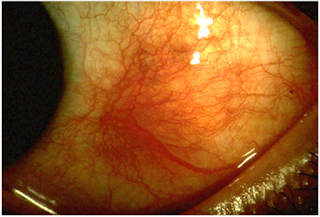

![]() |

| Fig:- Episcleritis |